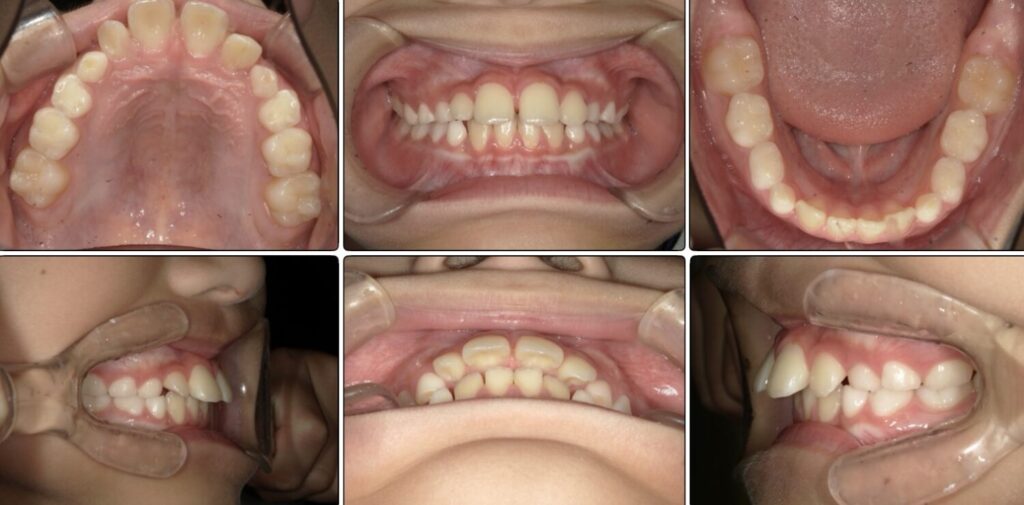

初診時上の前歯が下の歯に比べて前に飛び出ている状態、

いわゆる『出っ歯』の状態を気にされて来院されました。

治療前 / 現在

治療開始時

現在

上の歯の歯の軸の角度が変わり下顎が前方に誘導されました。

また下の歯の3番目のあたりにスペースができています。

毎日頑張ってくれている効果が出ています。